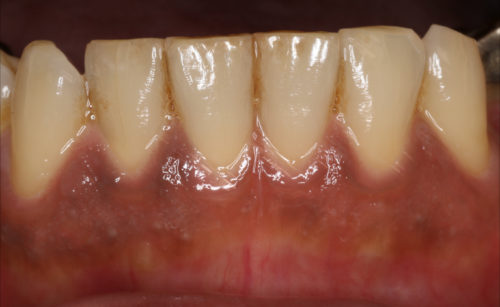

ズバリ原因はタバコです、解決法としては薬液を塗るだけです

処置は30分もあれば十分で、麻酔などはいりません

術後は若干ピリピリする感じがある、と言われますが、痛み止めを飲むほどではありません

着色が濃い方は1回では取りきれない部分もあり、2、3回処置を行うこともあります